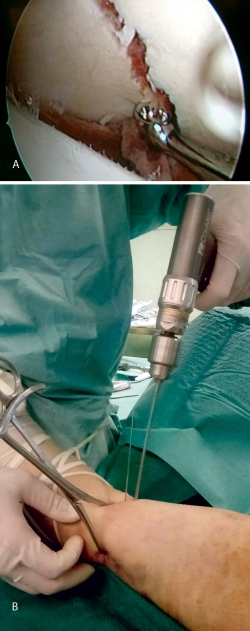

La artroscopia comenzó a utilizarse para asistir/controlar la reducción de las fracturas de meseta tibial, ya que la rodilla es la articulación en la que comenzó la artroscopia (Figura 1).

A raíz del artículo de Caspari(11), comenzamos a utilizar la artroscopia en nuestro medio en las fracturas de meseta tibial Schatzker de tipo II, en las que realizábamos la elevación del fragmento hundido mediante el uso de impactores desde la zona diafisometafisaria de la tibia, relleno del defecto con cemento biocompatible y fijación con tornillos canulados con arandela. Publicamos nuestra experiencia en los Cuadernos de Artroscopia en 1998(12)(Figuras 2 y 3).

Figura 1. Visión del cirujano de la reducción articular en una fractura de meseta tibial.

Figura 2. Técnica quirúrgica en fracturas de meseta tibial asistidas por artroscopia: elevación del fragmento hundido mediante impactor.

Figura 3. Técnica quirúrgica en fracturas de meseta tibial asistidas por artroscopia: relleno con cemento biocompatible y fijación con tornillos canulados de esponjosa.